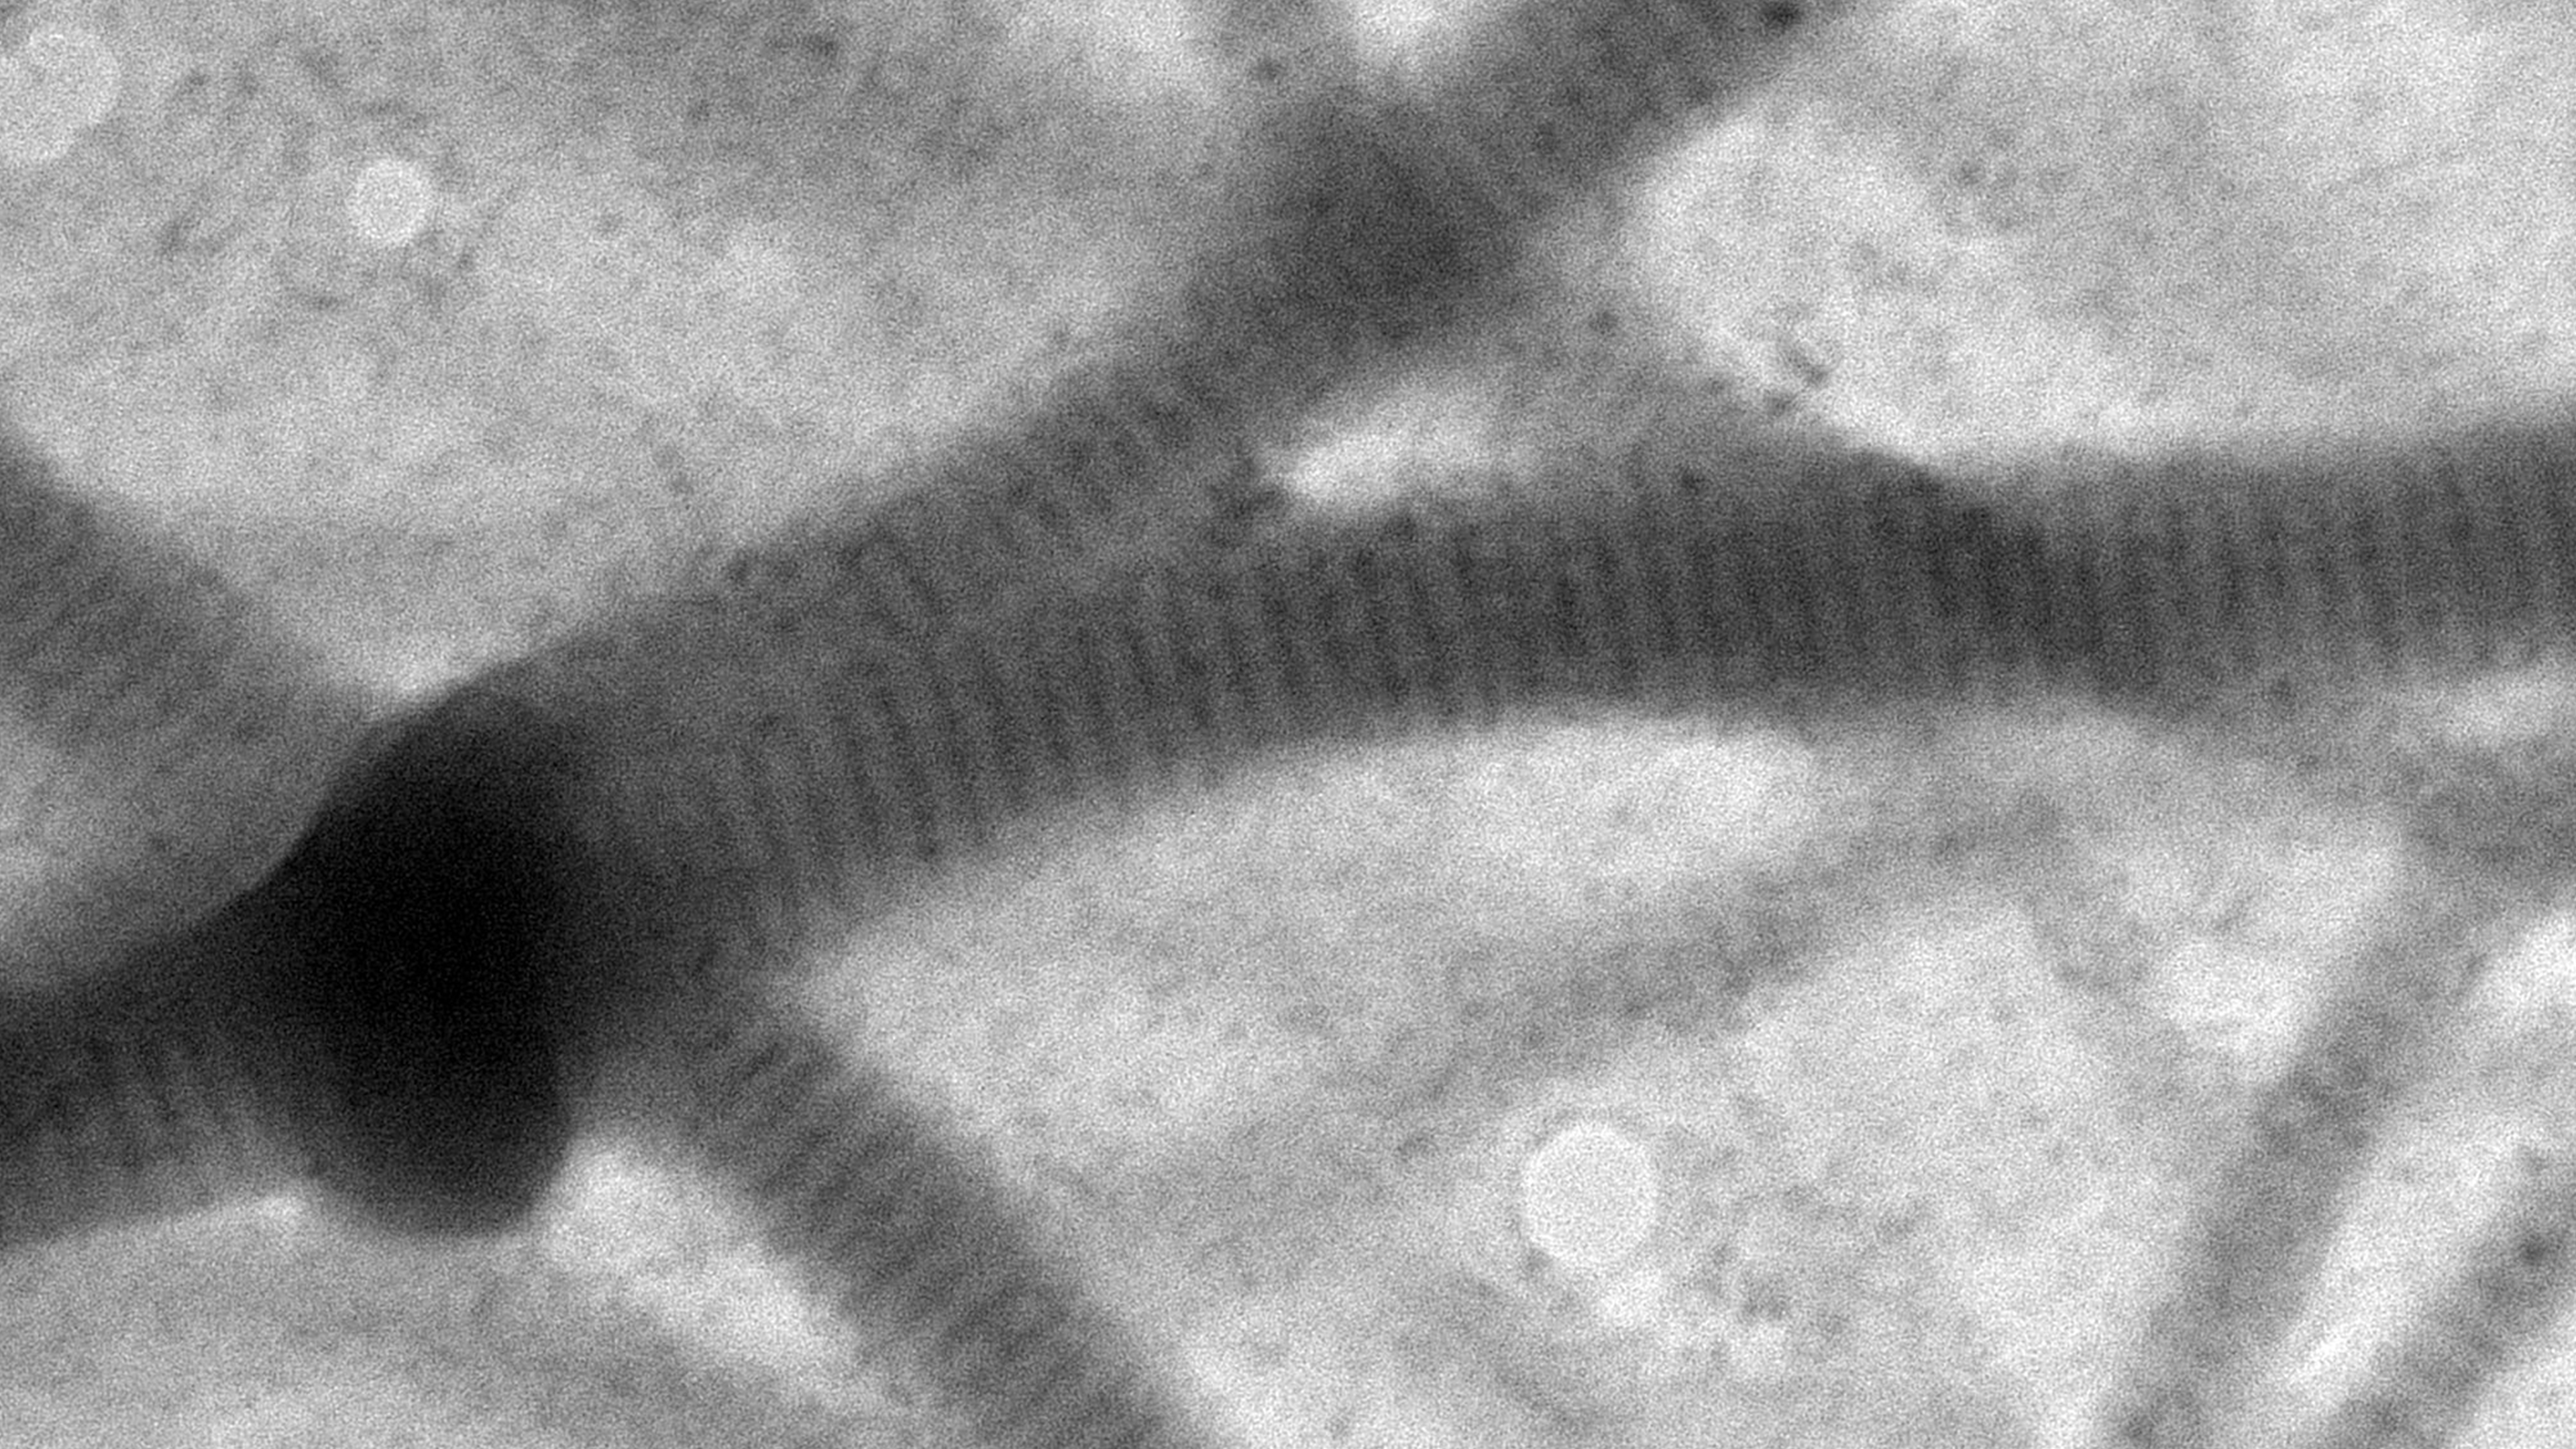

Cierra Divers, ‘27, and Ryan Dillard, ‘27

Cierra Divers, ‘27, a chemistry major with a psychology minor, and Ryan Dillard, ‘27, a biochemistry & molecular biology major, conducted research with Christine Helms, associate professor of physics, during the summer 2024, as part of the Integrated Inclusive Science post-first year research experience. Their research investigated fibrin fiber and fibrin film formation through microscopy. The Transmission Electron Microscope (TEM) image shows the repeating structure of fibrin fibers, which are a primary element in blood clots and are responsible for the strength of the clot. Fibrin film, which was overlooked for many years, was recently identified as an important antimicrobial barrier. The research by Divers and Dillard looks to deepen our understanding of the distinction between fibrin fibers and fibrin film.